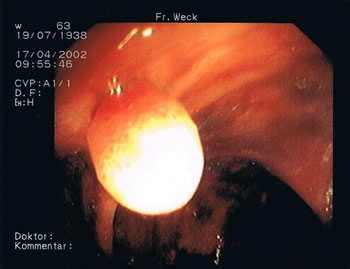

Endoskopische Bilder. Das Darmlumen innerhalb der einzelnen Darmabschnitte kann eher rundlich, leicht eingeengt oder dreieckförmig aussehen, entsprechend des anatomischen Aufbaus (s. Abb.1-4). Grundsätzlich gibt es verschiedene Arten von Polypen mit unterschiedlichen Konfigurationen und von verschiedener Größe. Kugelig(Abb.6) mit schmaler Verbindung zur Darmwand, hügelig mit breiter Basis, muschelförmig, die sich häufig an eine Querfalte anschmiegen, gestielte Polypen, die über einen Stiel mit der Darmwand verwachsen sind und sessile Polypen (Abb.5), die breitbasig auf der Darmwand aufsitzen. Der Übergang zum Dünndarm (Ileocaecal-Klappe) kann des Öfteren ein polypöses Aussehen vortäuschen (Abb.4).